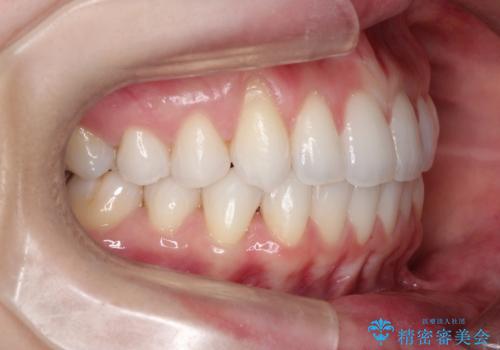

- 主訴:「右上犬歯を引っ込めて、歯並びをキレイにしたい」

右上の八重歯を気にされてご来院されました。結婚式を控えていたため挙式にまでに可能な限りキレイにしたいとのことでした。

右上の犬歯の歯茎は矯正前から退縮を起こしていましたが、矯正後もその退縮に関しては変化がありませんでした。今回は患者様が歯肉退縮に関しては治療をご希望ではありませんでしたが、当院ではこのように歯茎が下がり露出した根面を、歯茎を移植することでカバーし見た目を改善する手術を行っています。